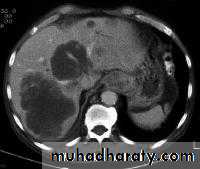

LEFT: Dilated esophagus (arrows) appears as long, well-defined structure paralleling heart RIGHT: Dilated esophagus usually deviates to right. Narrowing (arrow) at hiatus.

LEFT: CT shows dilated esophagus (arrow) that led to esophagram.RIGHT: Esophagram shows narrowing (arrow) at level of hiatus.